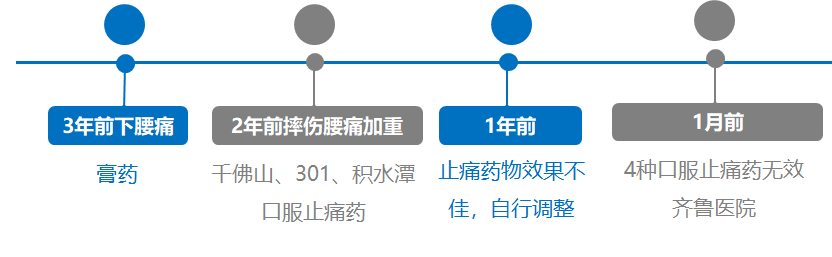

病例信息:M/57Yr,脊柱后凸畸形合并腰椎滑脱

病史:男,57岁,腰痛3年加重1月,既往体健

时间轴: